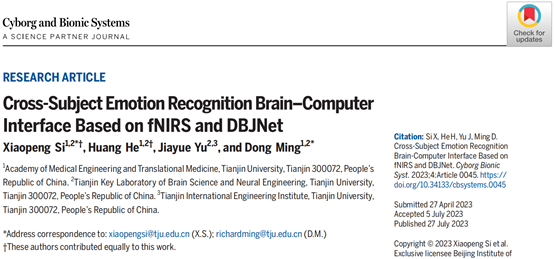

研究人员在本研究中共招募18名健康受试者(平均年龄为 23.4岁)参与视频情绪诱发实验,通过采用视频刺激诱导被试情绪。刺激情绪包括积极情绪(快乐)、中性情绪和消极情绪(悲伤)3种情绪。本研究通过利用LABNIRS设备采集被试的血氧浓度值(氧合血红蛋白【HbO】和脱氧血红蛋白【HbR】),采样率设为4 Hz,波长分别为780、805和830 nm。通过由15个光源和16个检测器组成的40个通道,覆盖双侧额上回、额中回、额下回、颞中回、颞上回、缘上回和角回(图1)。

图1. fNIRS通道配置信息。(A)fNIRS记录通道的地形分布。(B)佩戴近红外光谱传感器的受试者。